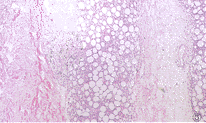

脂膜炎分類2.病理檢查 主要病變在脂肪層中分3 期:

(1)急性炎症期:發生脂肪細胞變性和細胞間炎症浸潤,包括中性粒細胞、淋巴細胞和組織細胞,以中性粒細胞為主,且常見有中性粒細胞核破壞,但不形成膿腫。

(2)巨噬細胞期:以組織細胞浸潤為主,吞噬脂肪後而成為泡沫狀巨噬細胞,並有少量淋巴細胞、漿細胞和中性粒細胞浸潤,往往也可見有多核巨細胞。

(3)成纖維細胞期:病變中主要為成纖維細胞和淋巴細胞,並有大量增生的纖維組織。

在病變演變過程,中、小血管也有改變,主要為血管周圍細胞浸潤、內膜增厚及類纖維蛋白變性。大網膜、腸系膜、心包膜、肝、脾、骨髓及腎上腺周圍脂肪中均有同樣的病理改變。肝臟內有瀰漫性脂肪壞死和脂肪浸潤。肺的病理改變為肺泡腔及間質炎性細胞浸潤、肉芽腫性肺炎及脂肪栓塞。